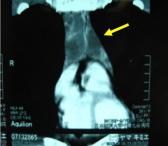

(2)右肺癌+巨大胸壁転移の症例に対して右肺上葉切除+縦隔リンパ節郭清ならびに胸壁転移切除・腹直筋による胸壁再建術(下図)。

胸部 CT:巨大胸壁転移

術中所見:胸壁合併切除 (第6,7,8,9,10肋骨切除)